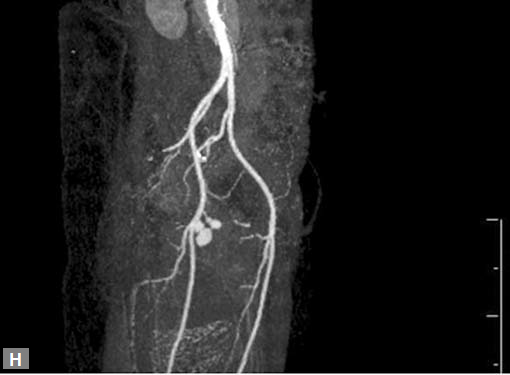

Figs 19A to Y (A to C) Scannogram (A), plain (B) and contrast study (C) show partial anomalous pulmonary venous connection; (D to F) Heterotaxy; (G) Aortic occlusion; (H and I) Aortic stents; (J) Aortic dissection with ‘Benz’ sign due to second dissection within the true lumen; (K, L and M) Aortic dissection with thrombus in pseudolumen following catheter angiogram; (N) Aortic dissection involving common carotid arteries and subclavian artery; (O, P, Q and R) Aortic dissection with right renal artery arising from true lumen and left renal artery from false lumen; (S, T, U and V) Stanford B dissection with extension Y to iliac vessels; (W to Y) Aneurysmal dilation of ascending aorta